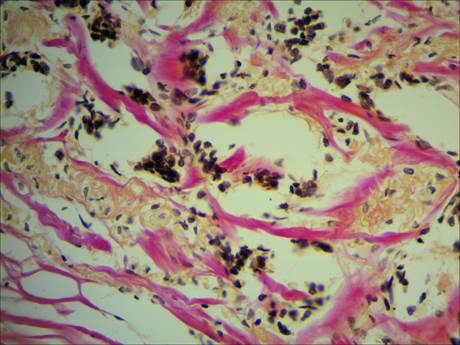

Карнификация Легкого: Микропрепараты и Диагностика

Раздел: Калейдоскоп образов